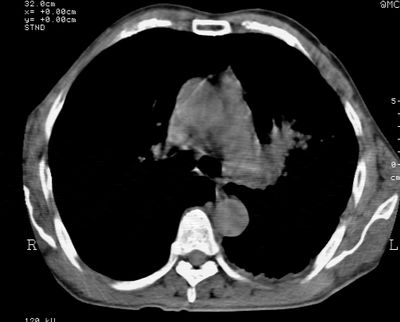

标题: CT24000:M65,胸痛,胸闷月余,既往慢支,肺气肿,肺心病 [打印本页]

标题: CT24000:M65,胸痛,胸闷月余,既往慢支,肺气肿,肺心病

左肺门肿块,相应支气管闭塞,左肺上叶、舌叶大片及散在高密度影,部分呈不张改变,两肺纹粗乱,左侧胸腔积液。考虑左侧中央型肺癌伴阻塞性改变。

左肺门见巨大软组织肿块影,直径约--,境界清,左上肺叶支气管变窄,左上肺舌叶见大片状密实影,余肺纹理增多、紊乱、纤细、部分网格状,两肺透亮度增高,纵隔内见增大多发淋巴结影,心影略左偏,左侧少量胸腔积液。

左侧中央型肺癌伴左上肺舌叶不张、纵隔淋巴结转移,左侧少量胸腔积液。